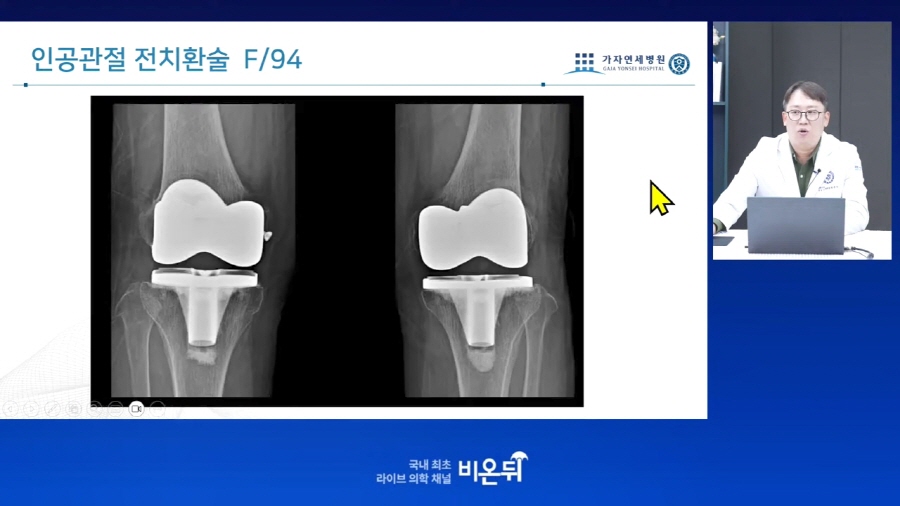

연골을 재생하는 치료와 무릎에서 마지막으로 할 수 있는 인공관절 수술까지 차례로 사례를 바탕으로 강의를 진행해주시고,